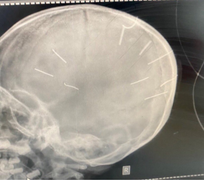

(VTC News) - Kết quả phim chụp X-quang cho thấy, bé Đ.N.A., 3 tuổi, ở Canh Nậu, Thạch Thất, Hà Nội có đinh trong sọ, tiên lượng tử vong cao.